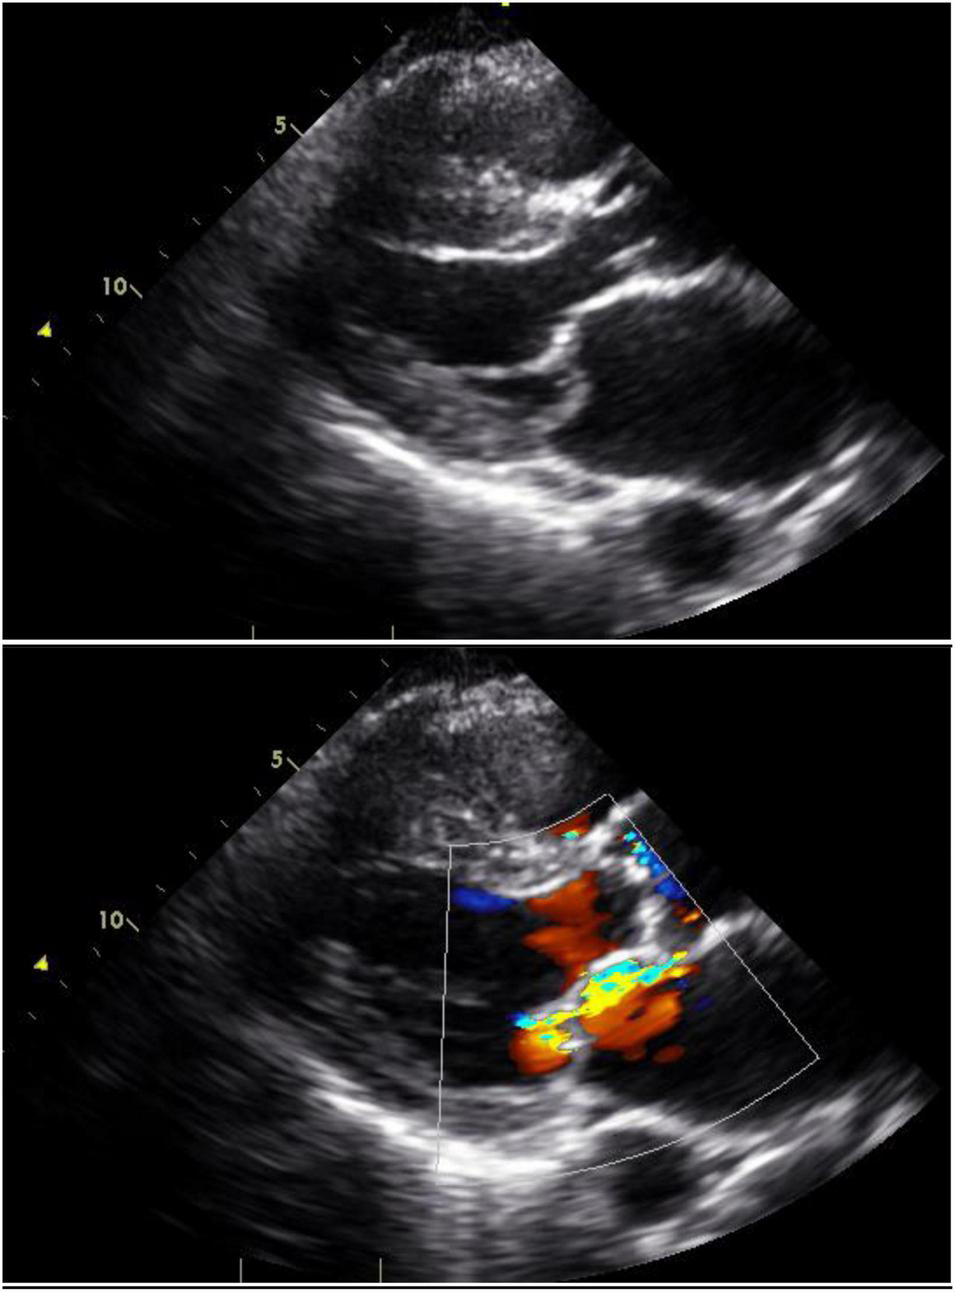

Mitral Valve Regurgitation

Mitral regurgitation is most commonly due to mitral valve prolapse (Figure 3). Indeed, primary mitral valve prolapse (MVP) due to myxomatous valve disease is the most common valvular disease in pregnancy (41). MVP is usually suspected or diagnosed with clinical findings of systolic click and mitral regurgitant murmur, but these findings may not be classical in pregnancy because of the volume increases and lower systemic resistance that occur in pregnancy (42, 43). The diagnosis is confirmed and the severity of mitral regurgitation ascertained by echocardiography (Figure 3).

FIGURE 3

Mitral valve prolapse: Still images with and without color Doppler in a woman with mitral valve prolapse affecting the posterior leaflet. The posterior leaflet bows beyond the mitral annular plane and produces an anteriorly-directed jet of mitral regurgitation.

In the absence of other cardiovascular pathology, the majority of pregnant women with MVP and mild or moderate mitral regurgitation have an uneventful pregnancy. Asymptomatic women with mitral valve prolapse and chronic, severe regurgitation usually tolerate pregnancy without significant complication although the increased cardiac volume may be associated with signs and symptoms of volume overload and atrial fibrillation. This can generally be managed with careful diuresis and beta blockers (16, 42, 44). Metoprolol can be safely used in pregnancy but may be associated with fetal bradycardia so should be used judiciously.